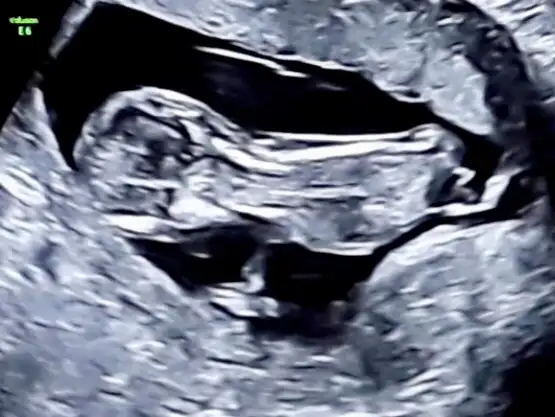

Bence bu hepsini yalanlıyor 6 haftalık kız 7 haftalık erkek gibi duruyor. Demekki bebeğin yeri surekli değişiyor teori yalan

Zaten erken usgye bakılıyor bebeğin yeri değişmeden önceki haline yani. O yüzden 6 haftalık olanı daha çok önemsiyorlar 7 haftalık olanda ortaya gelmiş artık bebek. Yinede çok bilimsel değil bu teori bende teoriye bakınca kız düşündüm. 7 haftalık da ortada olduğu için mi erkek dediniz merak ettimBence bu hepsini yalanlıyor 6 haftalık kız 7 haftalık erkek gibi duruyor. Demekki bebeğin yeri surekli değişiyor teori yalan

6 haftalık sağ tarafta 7 haftalık sola yakın. Ben 5 haftalıkken kanama şikayeti ile dr a gittim .dr bebek yerleşmeye çalışıyor kesenin içinde sürekli yer değiştiriyor uygun yer bulana kadar oyüzden kanama olabilir dedi.Zaten erken usgye bakılıyor bebeğin yeri değişmeden önceki haline yani. O yüzden 6 haftalık olanı daha çok önemsiyorlar 7 haftalık olanda ortaya gelmiş artık bebek. Yinede çok bilimsel değil bu teori bende teoriye bakınca kız düşündüm. 7 haftalık da ortada olduğu için mi erkek dediniz merak ettim